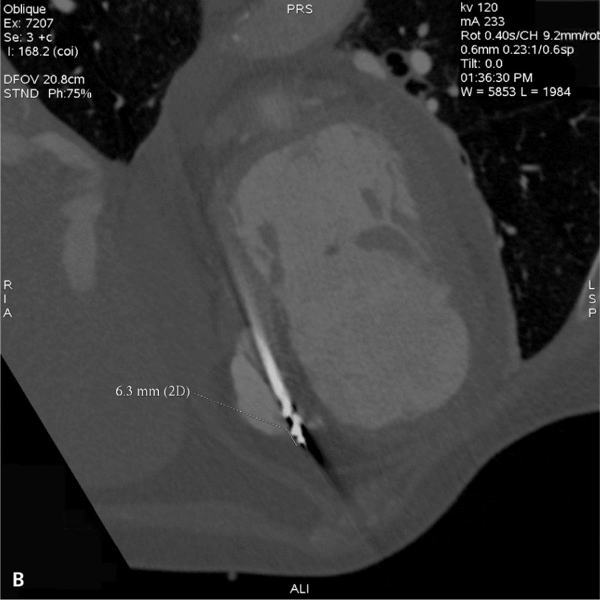

• przemieszczenie końcowego odcinka elektrody poza światło prawej komory uwidocznione dopiero po ponownej prośbie kardiologa, aby zwrócić uwagę na położenie końcówki elektrody, co wymagało zmiany szerokości i długości okna rekonstruowanego (często nie udaje się postawić rozpoznania z powodu masywnych artefaktów od elektrody) (ryc. 1A, B),

RYCINA 1. Badanie serca metodą TK. [A] Warstwa poprzeczna na standardowym oknie. Masywne artefakty od elektrody całkowicie uniemożliwiają ocenę jej położenia względem ściany prawej komory. [B] Warstwa rekonstrukcji MPR w linii elektrody po odpowiednim ustawieniu okna. Dystalny odcinek elektrody nieznacznie przemieszczony o 5 mm poza światło prawej komory.